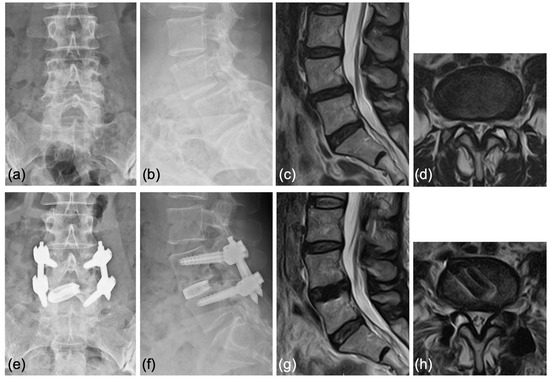

Case 2: A 63-year-old woman was diagnosed with degenerative spondylolisthesis of the L4 vertebra with instability by X-ray, CT, and MRI. VAS for back pain was 10 mm and leg pain 40 mm, and the JOA score was 21/29. After the failure of conservative treatment, PETLIF was performed. One month after surgery, the VAS of leg pain improved significantly to 0 mm, whereas back pain was 10 mm. Postoperative X-ray and MRI showed spondylolisthesis was well reduced comparable to case 1 (Figure 9e–h).

Figure 9.

(a,b) Preoperative X-ray showing 2° L4 spondylolisthesis. (c,d) Preoperative MRI showed lumbar spinal stenosis at the L4/5 level. (e,f) Postoperative X-ray showed L4 spondylolisthesis was well reduced. (g,h) Postoperative MRI showed that the spinal canal area was expanded.